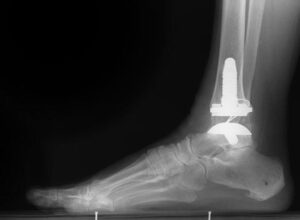

An X-ray of a total ankle replacement (arthroplasty).

Total Ankle Replacement (Arthroplasty): Restoring Joint Function

Total ankle replacement, or arthroplasty, is a surgical procedure where the damaged cartilage and bone in the ankle joint are removed and replaced with metal or plastic components. These artificial joint surfaces are designed to restore movement and improve overall joint function.